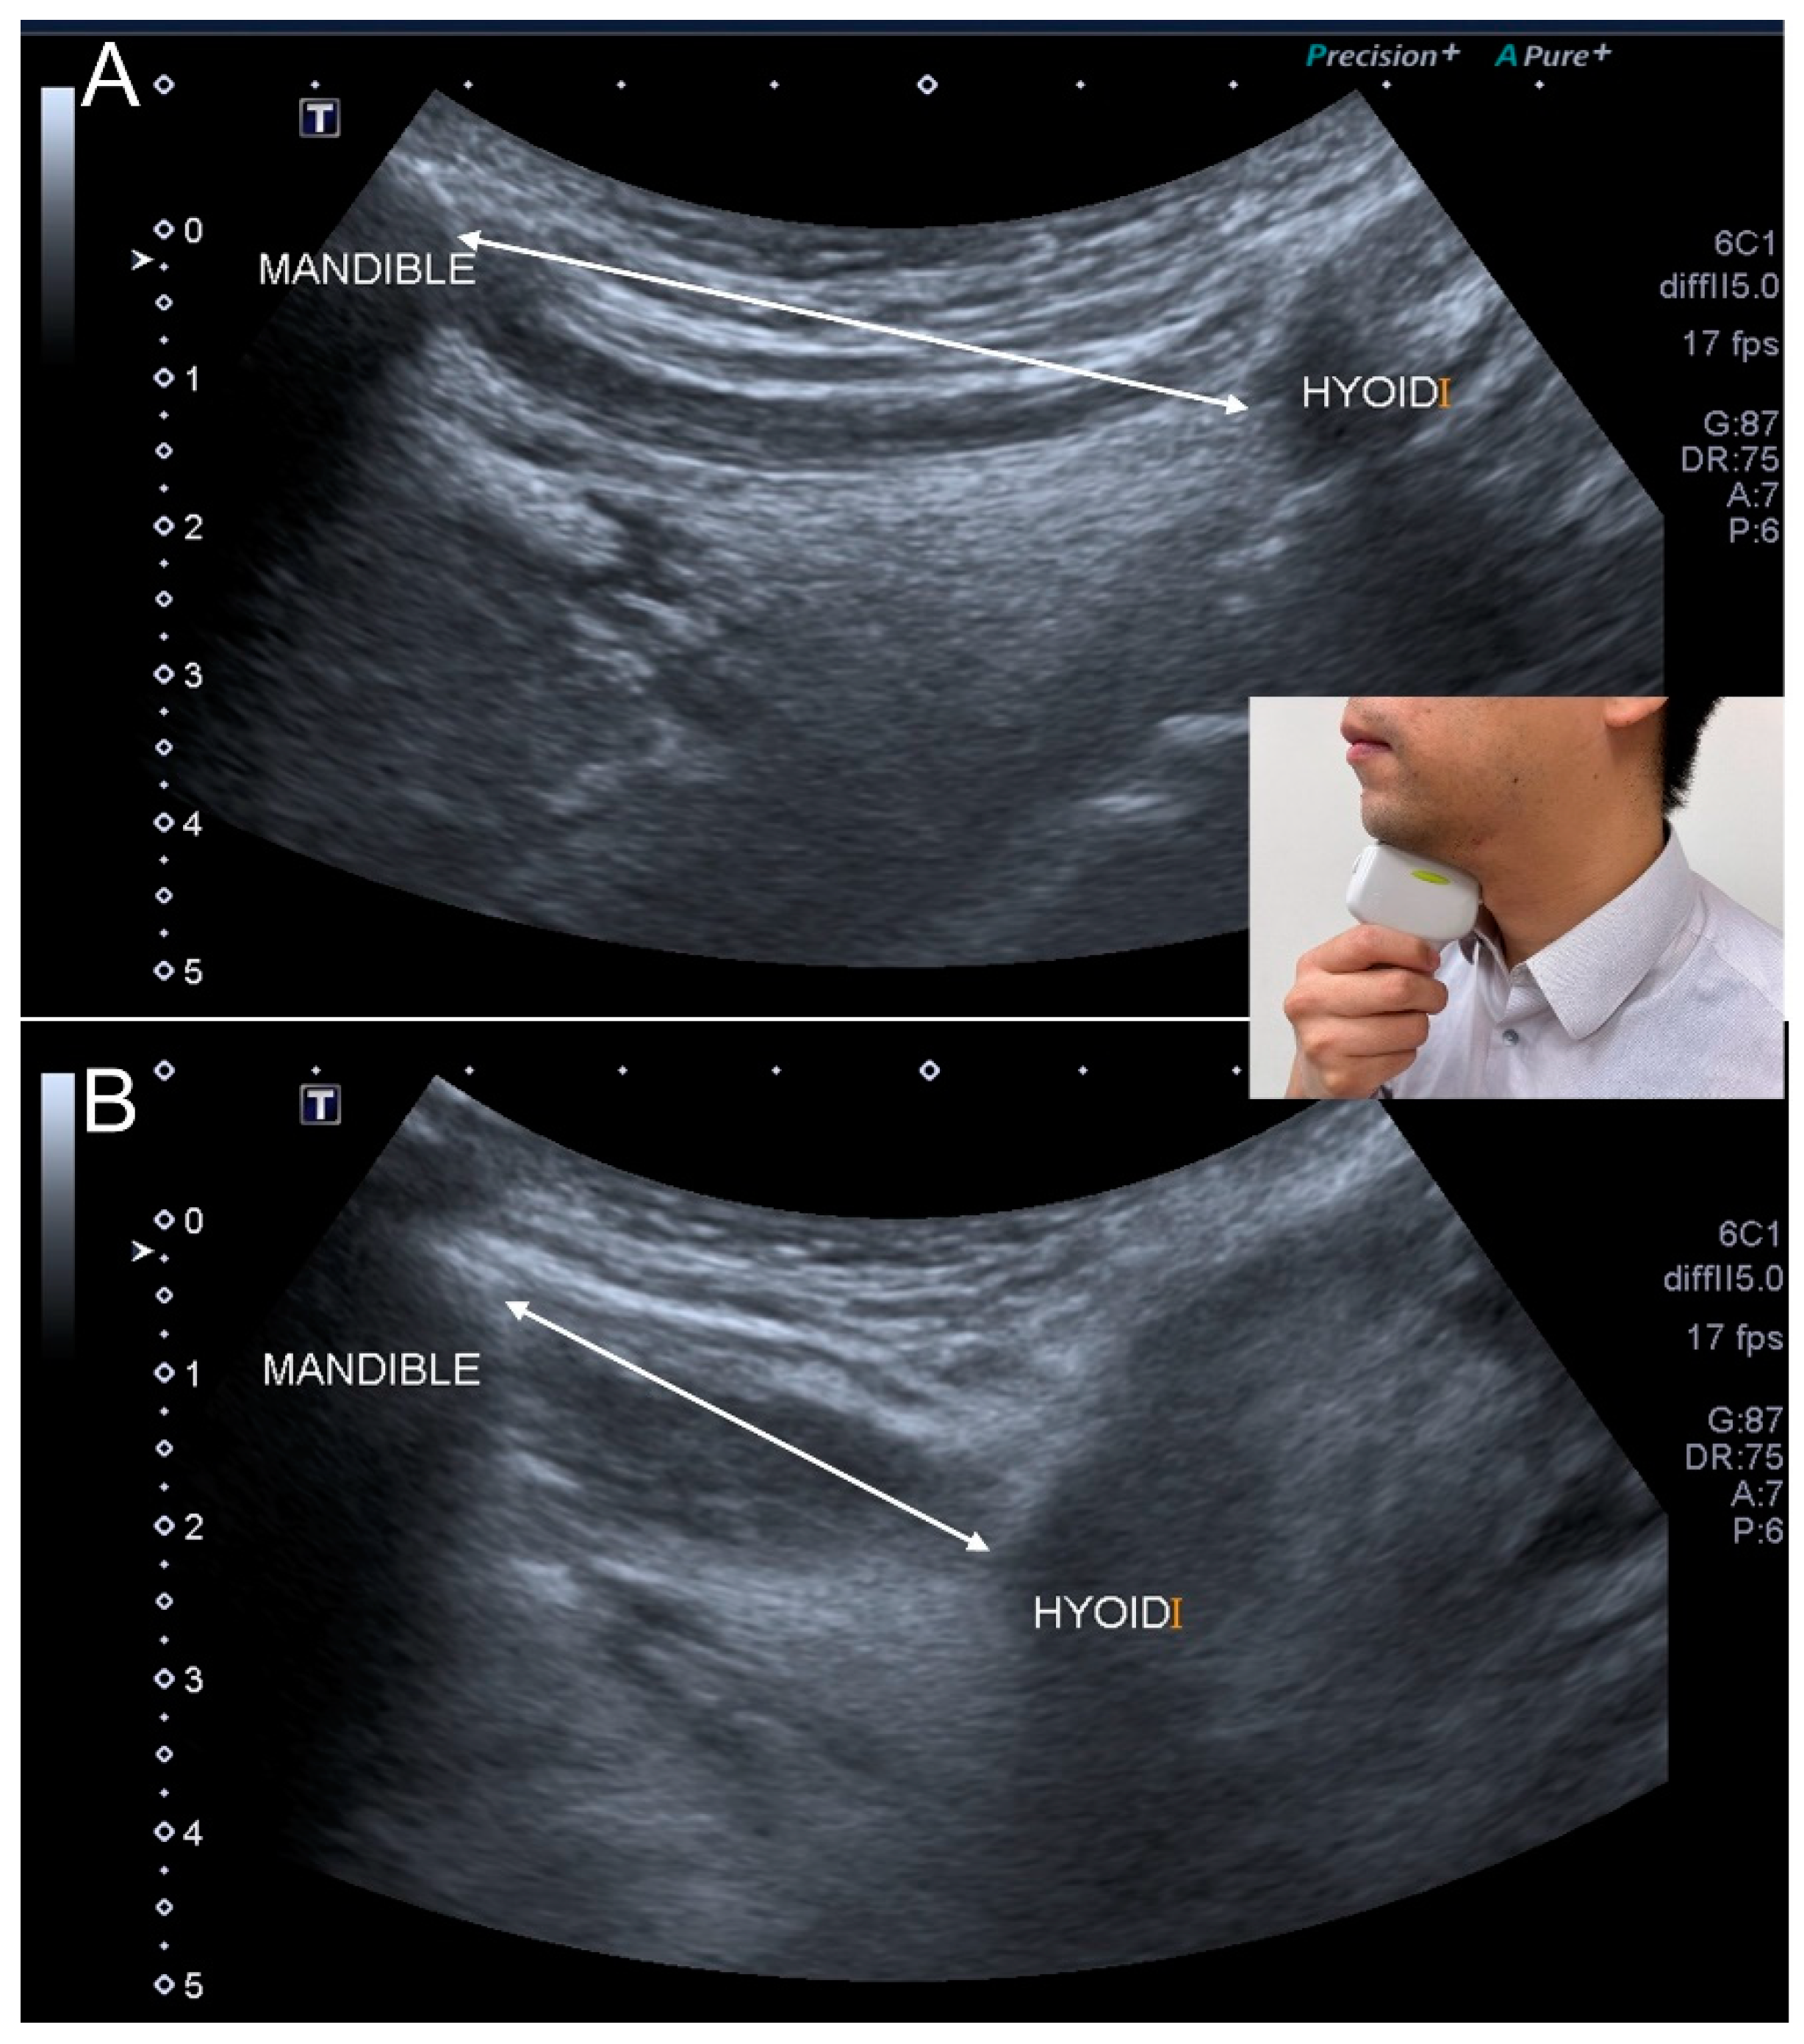

3.9. Ultrasonography

- Ogawa, N.; Mori, T.; Fujishima, I.; Wakabayashi, H.; Itoda, M.; Kunieda, K.; Shigematsu, T.; Nishioka, S.; Tohara, H.; Yamada, M.; et al. Ultrasonography to Measure Swallowing Muscle Mass and Quality in Older Patients With Sarcopenic Dysphagia. J. Am. Med. Dir. Assoc. 2018, 19, 516–522. [Google Scholar] [CrossRef]

- Mori, T.; Wakabayashi, H.; Ogawa, N.; Fujishima, I.; Oshima, F.; Itoda, M.; Kunieda, K.; Shigematsu, T.; Nishioka, S.; Tohara, H.; et al. The Mass of Geniohyoid Muscle Is Associated with Maximum Tongue Pressure and Tongue Area in Patients with Sarcopenic Dysphagia. J. Nutr. Health Aging 2021, 25, 356–360. [Google Scholar] [CrossRef] [PubMed]

- Ogawa, N.; Wakabayashi, H.; Mori, T.; Fujishima, I.; Oshima, F.; Itoda, M.; Kunieda, K.; Shigematsu, T.; Nishioka, S.; Tohara, H.; et al. Digastric muscle mass and intensity in older patients with sarcopenic dysphagia by ultrasonography. Geriatr. Gerontol. Int. 2021, 21, 14–19. [Google Scholar] [CrossRef] [PubMed]

| Ultrasonography | <1536 mm2 for the cross-sectional area of the tongue muscle <75.1 mm2 for the cross-sectional area of the digastric muscle |